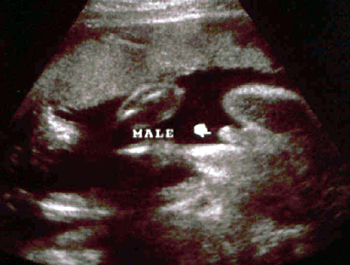

الولد

ولد في الأسبوع ال 15